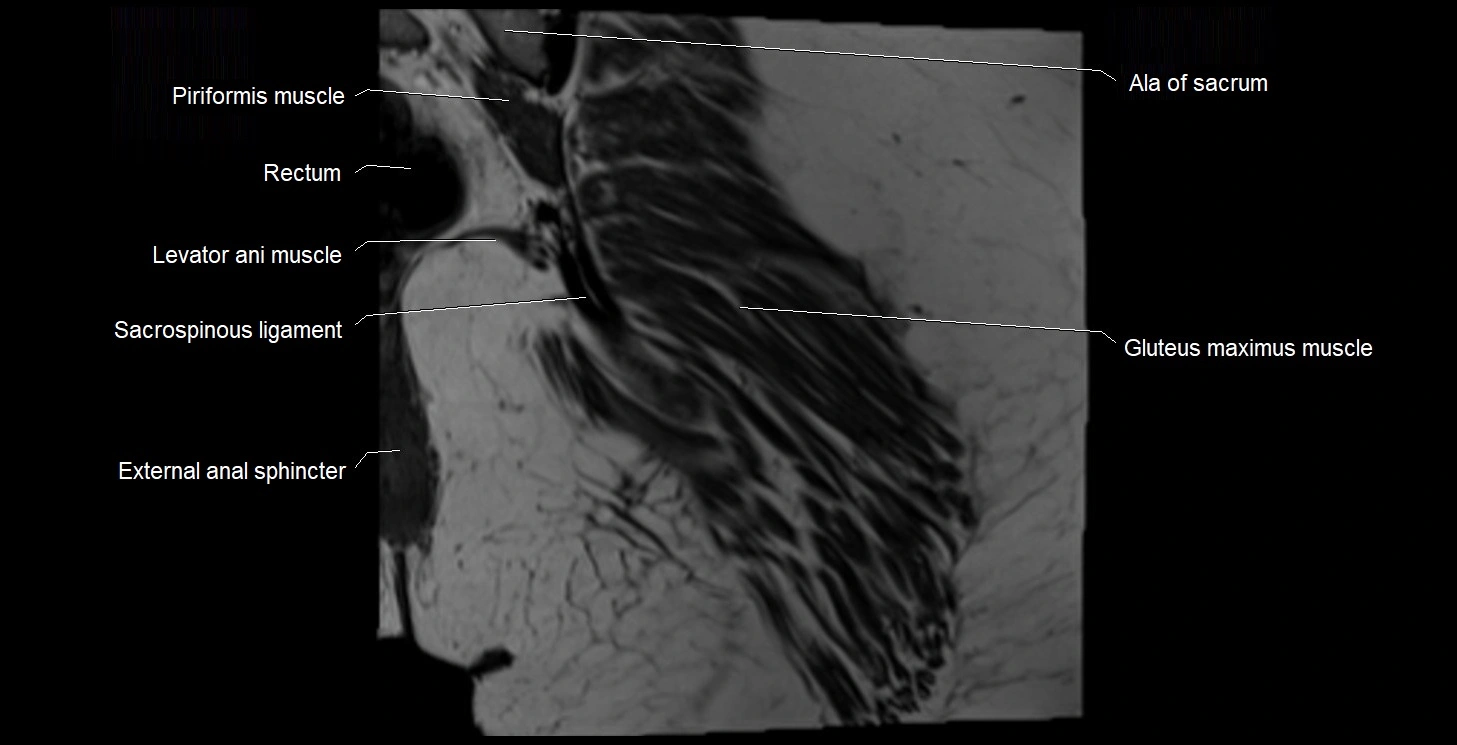

- Ala of sacrum

- External anal sphincter

- Gluteus maximus muscle

- Iliococcygeus muscle

- Levator ani muscle

- Rectum

- Sacrospinous ligament